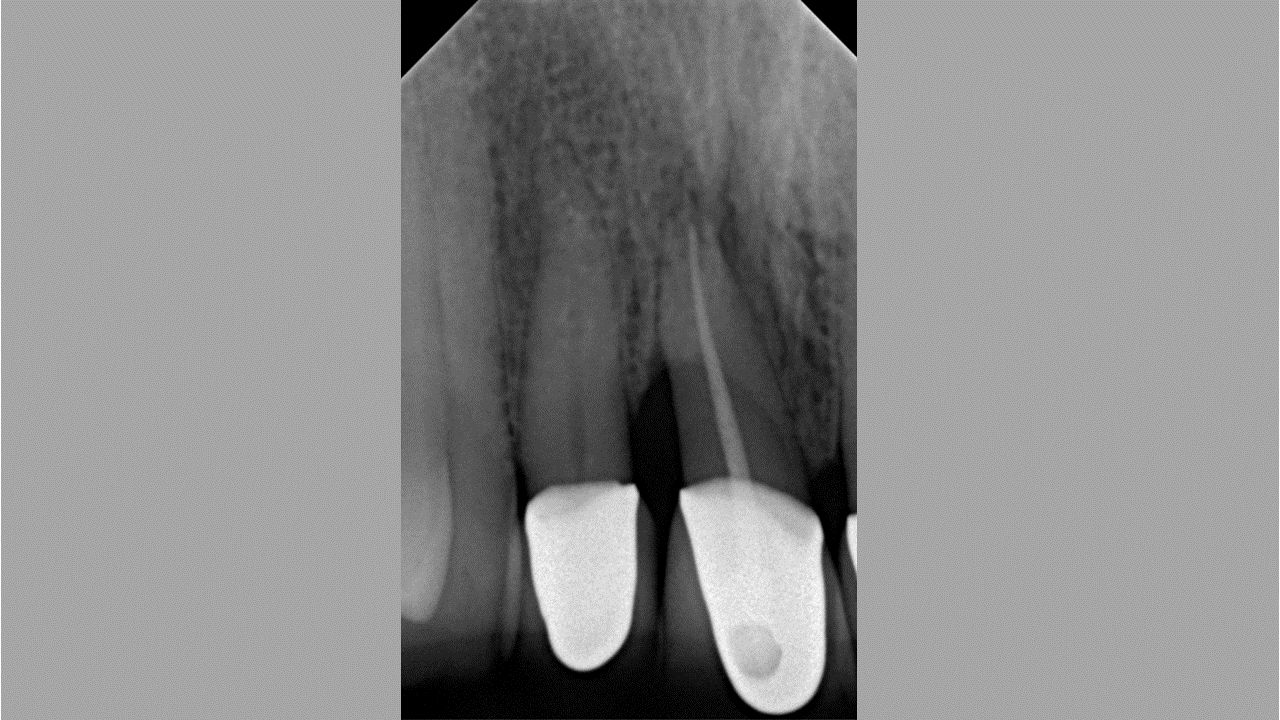

02/08 - Pre-operative radiograph of the defect reveals a deep intrabony defect on tooth 11.Non-contained intrabony defect treated with the simplified papilla preservation flap in conjunction with Straumann® Emdogain® and a particulate bone grafting material - Prof. Dr. Dr. A. Kasaj

08/08 - Radiograph of the defect 12 months post-operative shows a defect fill.Non-contained intrabony defect treated with the simplified papilla preservation flap in conjunction with Straumann® Emdogain® and a particulate bone grafting material - Prof. Dr. Dr. A. Kasaj